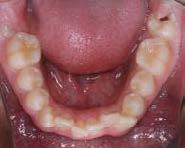

En las fotografías intraorales (Figura 3) observamos una clase II molar bilateral, clase II canina derecha, clase III canina izquierda, apiñamiento severo superior y moderado inferior, presencia de mordida abierta anterior y posterior a nivel de premolares (Figura 4), forma de arco triangular en la arcada superior y forma de arco oval en inferior, ausencia del OD 46 y presencia de un diente supernumerario.

Figura 2. Fotografías extraorales frente y perfil. Figura 3. Fotografías de frente, lateral derecha, lateral izquierda.

Figura 4. Vista oclusal superior e inferior. Figura 5. Frente, perfil.